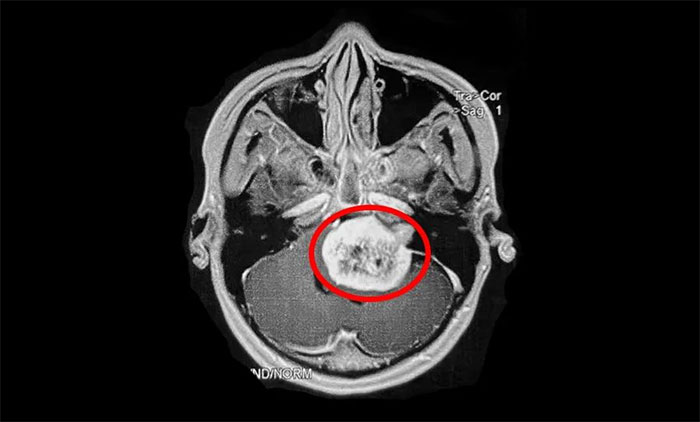

值得注意的是,听神经瘤早期表现易与耳聋及其他一些颅脑肿瘤混淆,出现相应症状时,患者应及早到具备专科诊疗能力的医疗机构,通过听力学检查、面神经功能检查、前庭功能检查、影像学检查(听神经瘤主要检查手段),即可明确诊断。

▲ 影像学检查是听神经瘤主要检查手段(示意图)